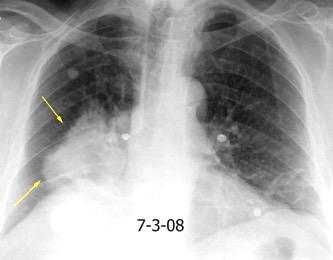

VIH+. 1 mes antes derrame pleural en el curso de una

infección

Huggins